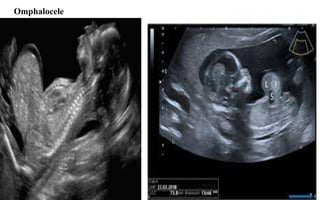

Omphalocele